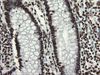

Applications FC, IF, IHC, WB

Recommended Dilution WB 1:1000, IHC 1:150, IF 1:100, FLOW 1:100